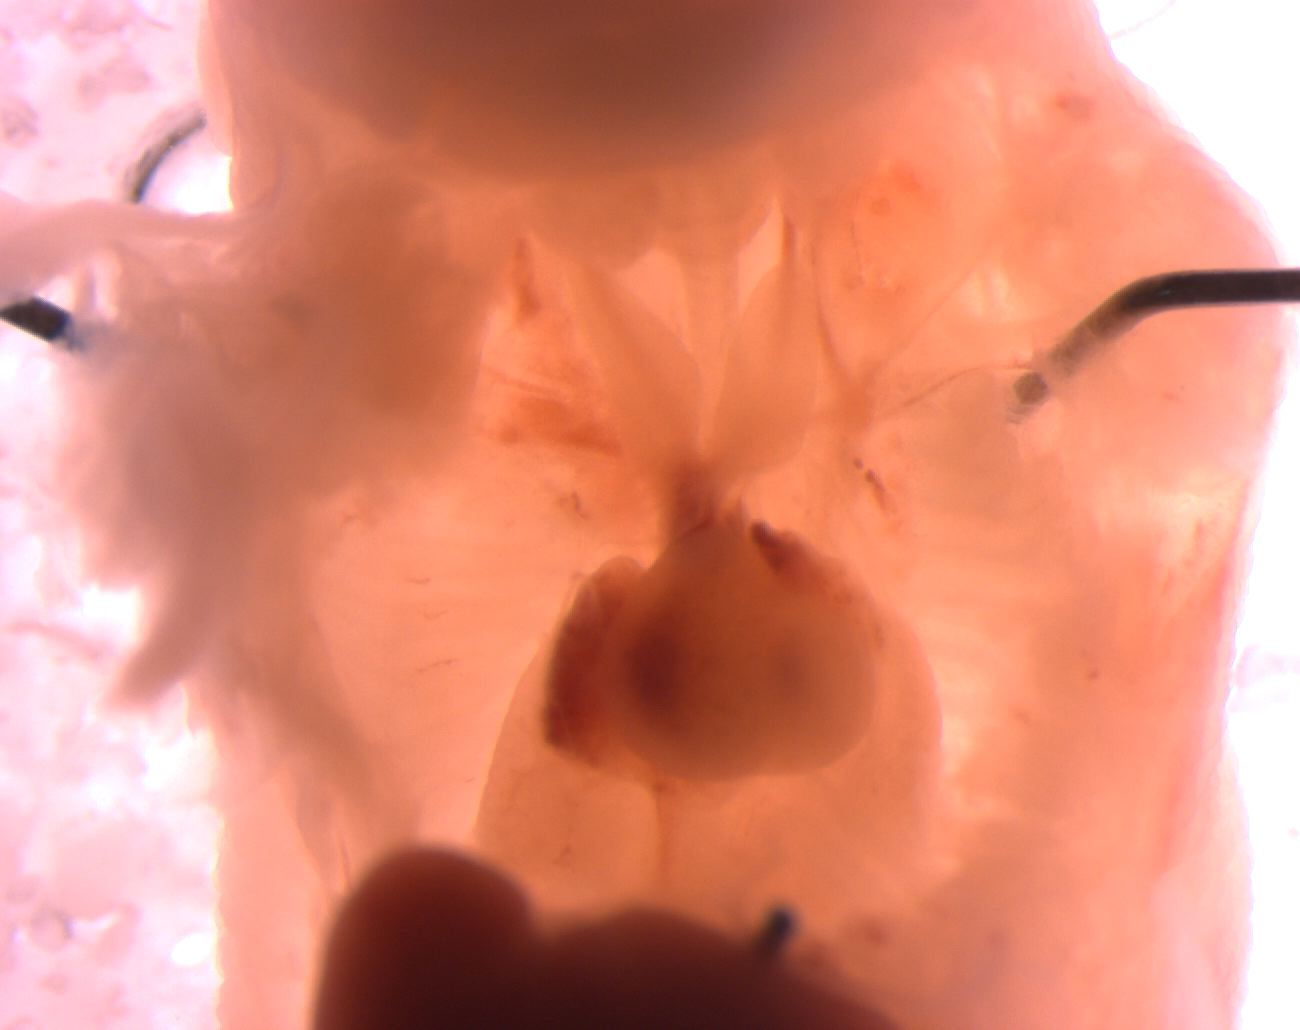

Caption Mutant 2588-003-2 (E16.5) has hypoplastic thymus

Copyright This image is from the Laboratory of Dr. Cecilia Lo, a member of the Cardiovascular Development Consortium (CvDC), Bench to Bassinet (B2B) program of the National Heart Lung and Blood Institute (NHLBI), and is displayed with the permission of the authors. J:175213

b2b2588Clo Mutant line 2588; Bench to Bassinet Program (B2B/CVDC), mutation 2588 Cecilia Lo

b2b2588Clo/b2b2588Clo C57BL/6J-b2b2588Clo